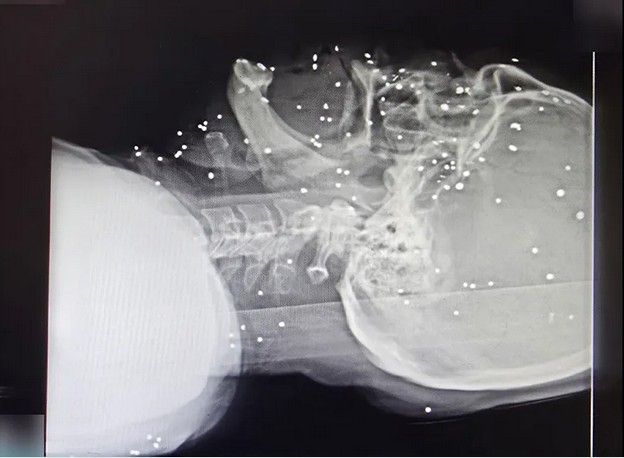

تصاویر رادیوگرافی معترضان نشان میدهد صورت انسانها به هدف تیراندازی تبدیل شدهاند. در چندین پرونده، صورت و سر مجروحان با دهها ساچمه فلزی پر شده است؛ ساچمههایی که در بافت نرم صورت، اطراف چشمها، بینی، فک و حتی نزدیکی جمجمه گیر کردهاند. این الگو با شلیکهای پراکنده و تصادفی همخوانی ندارد و بیشتر شبیه شلیک مستقیم و از فاصله نزدیک به چهره انسانهاست.

در تصویر رادیوگرافی سه تن از معترضان مجروح دیده میشود که در ناحیه سر، صورت و گردن هر کدام حدود ۱۰۰ ساچمه وجود دارد. تعداد ساچمهها در کنار پراکندگی وسیع، اندازه ریز و یکنواخت آنها و نفوذ برخی ساچمهها به جمجمه و بافتهای عمقی صورت، با مشخصات فشنگهای ساچمهریز (Birdshot) تطابق دارد. بر اساس اطلاعات پرونده این بیماران مجروحانی که در عکسهای شماره ۱ و ۲ رادیوگرافی آنها منتشر شده، پس از چند روز جان خود را از دست دادهاند.

«کیانا کثیری»، متخصص پزشک خانواده، که خود نیز در گروههای درمانی در جریان اعتراضات «زن زندگی آزادی» و همچنین اعتراضات دیماه امسال فعالیت داشته، در مورد این سه آسیبدیدگی میگوید: «این سه مجروح مورد اصابت تعداد متعدد ساچمه قرار گرفتند که بدون شک اندام چشم آسیب دیده، این مجروحان دچار التهاب و عفونت در ناحیه بافت گوشتی سر و صورت خواهند شد. از آنجا که در ناحیه صورت تمرکز رگهای خونی و رشتههای عصبی فوق العاده زیاد است، این مجروحان دچار دردهای فوقالعاده شدید خواهند شد که متاسفانه عمل جویدن و بلع را مختل میکند.

در مورد آسیب چشمی باید دید که آسیبدیدگی در چه حد و میزانی است. متاسفانه اگر درمان سریع انجام نشود و چشم عفونت کند مجبور به تخلیه چشم خواهند شد. در هر صورت آسیبدیدگی چشمی حاصل از اصابت ساچمهها باعث ضعف شدید قدرت بینایی خواهند شد.»